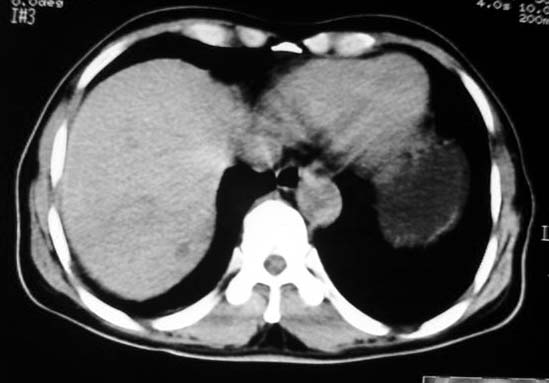

标题: CT7740:男65岁,无明显不适.

胃底与体交界侧壁一息肉样改变,以宽基与胃壁相连且胃壁僵硬,考虑胃恶性病变(胃癌?息肉恶变?)伴脾门淋巴结肿大可能性大。

定位:病灶位于胃腔外,大弯侧后下方.

特征:实质性肿物,边界清楚,内见低密度影,明显压迫胃壁,并形成切迹.

考虑:脾门淋巴瘤或间质瘤.

胃大弯侧,胃底与胃体交界处可见一圆形软组织肿块影,边缘较光整,内部密度较均匀

考虑:胃平滑肌瘤

考虑胃的肿瘤或胰尾肿瘤,肝右叶后下段低密占位警惕转移。建议增强检查

从这些图像上看,此软组织团块影,在胃腔的外面,胃壁是一种受压的改变,所以考虑此病灶和胃没有关系,建议进一步增强ct检查。

病灶起源于胃壁向腔内外突出,边缘光整,内可见片状低密度区,考虑胃壁非上皮性肿瘤可能性大